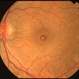

- full thickness macular hole

- A 32 years old female presents with complains of diminution of vision in right eye with Full thickness retinal hole involving the fovea.